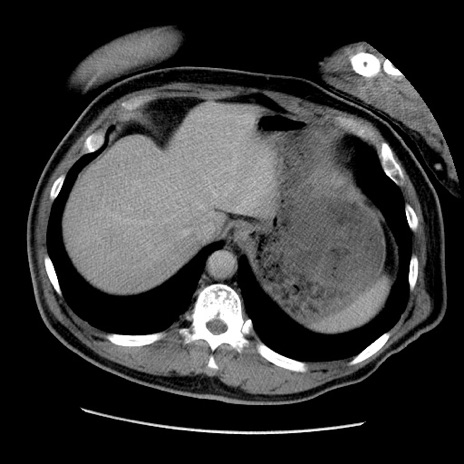

症例22(横断像)

【症例】50歳代男性

【主訴】腹痛

【現病歴】AVMからの被殻出血のため回復期リハ病棟入院中。 本日午後3時頃急に下腹部痛が出現した。

【既往歴】AVM、被殻出血、虫垂炎、高血圧

【身体所見】意識晴明、左半身不全麻痺、会話の理解は良好、36.5°C、腹部:膨隆、全体に板状硬、下腹部正中に圧痛点あり、反跳痛-、筋性防御不明、右下腹部にope scar

【データ】WBC 9400、CRP 0.06